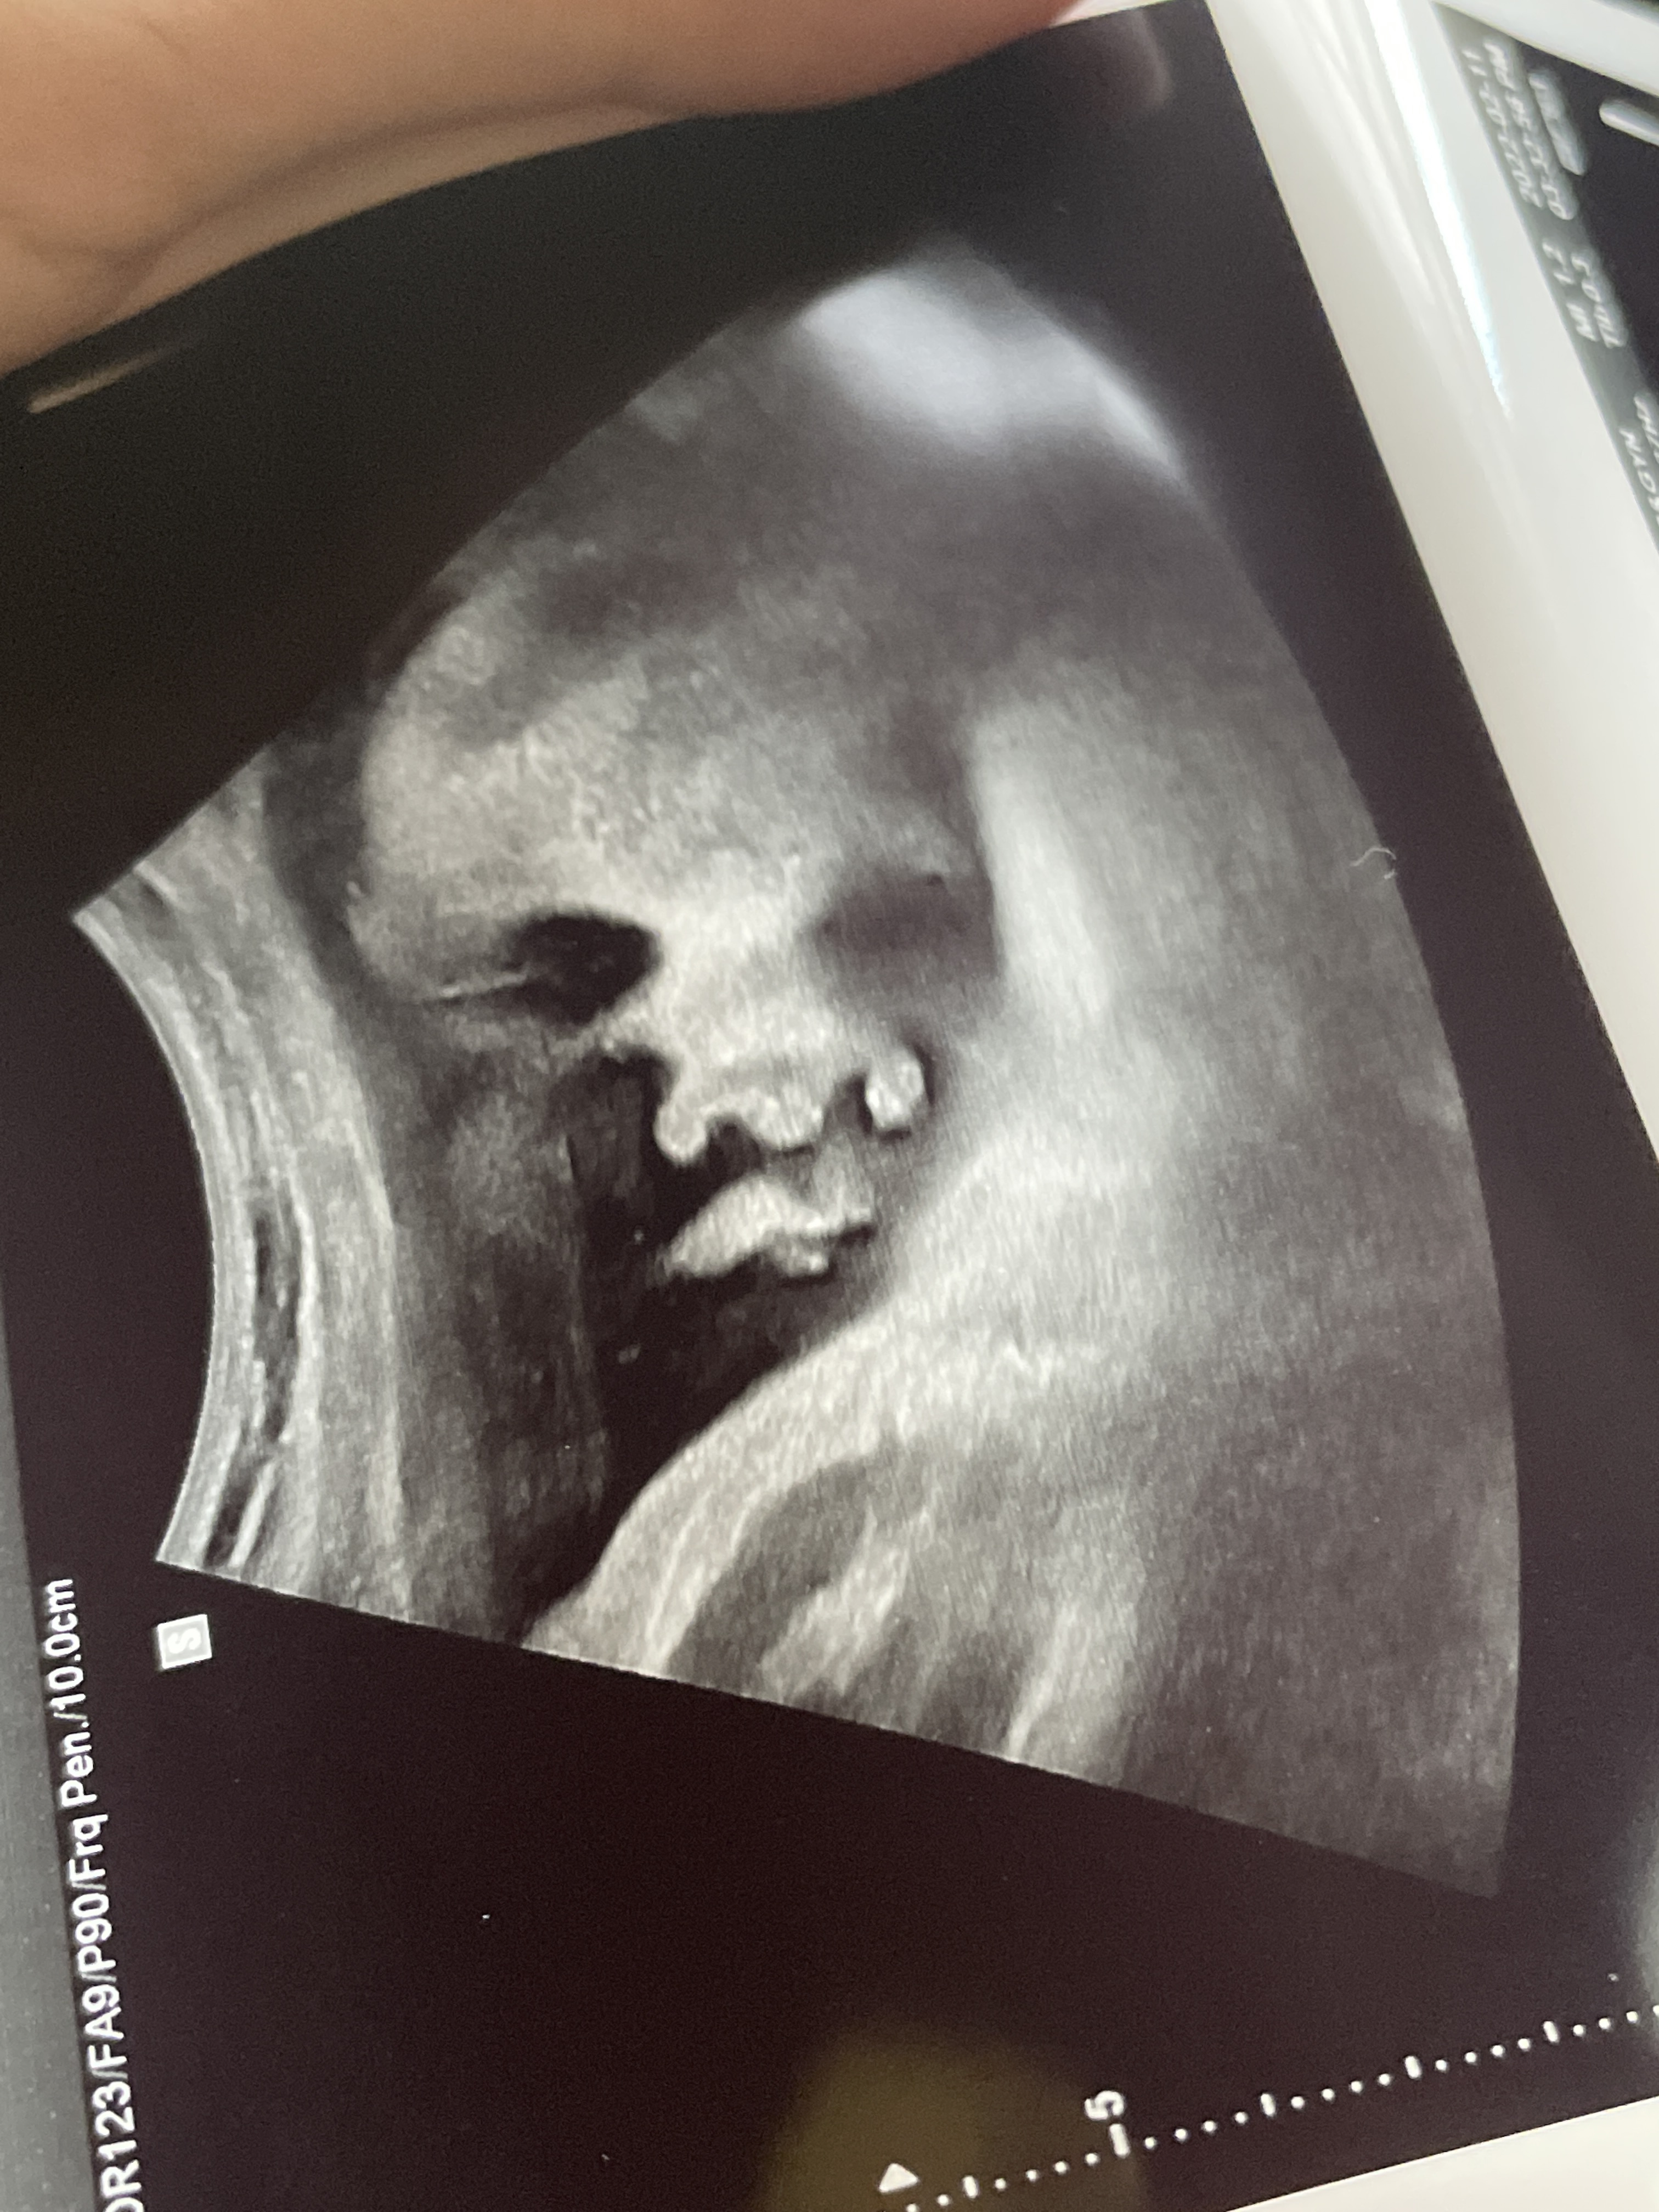

초음파 기기

초음파 사진이 선명하게 잘 나오는 편이었다.

그리고 애기 초음파 사진도 진짜 이쁘게 여러장 찍어주신다.

덕분에 내 태교 다이어리는 초음파 사진들로 풍년이다ㅎㅎ